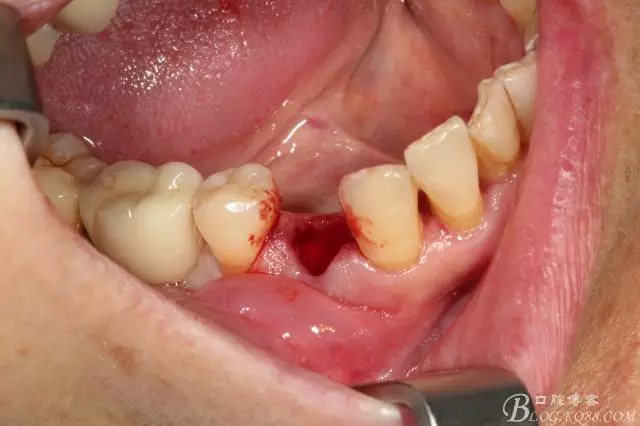

拔牙 當(dāng)然這種手術(shù)我必須不翻瓣零翻瓣

簡單備洞以后植入種植體 植體和頰側(cè)空間距離大于2毫米 注意沒有植骨